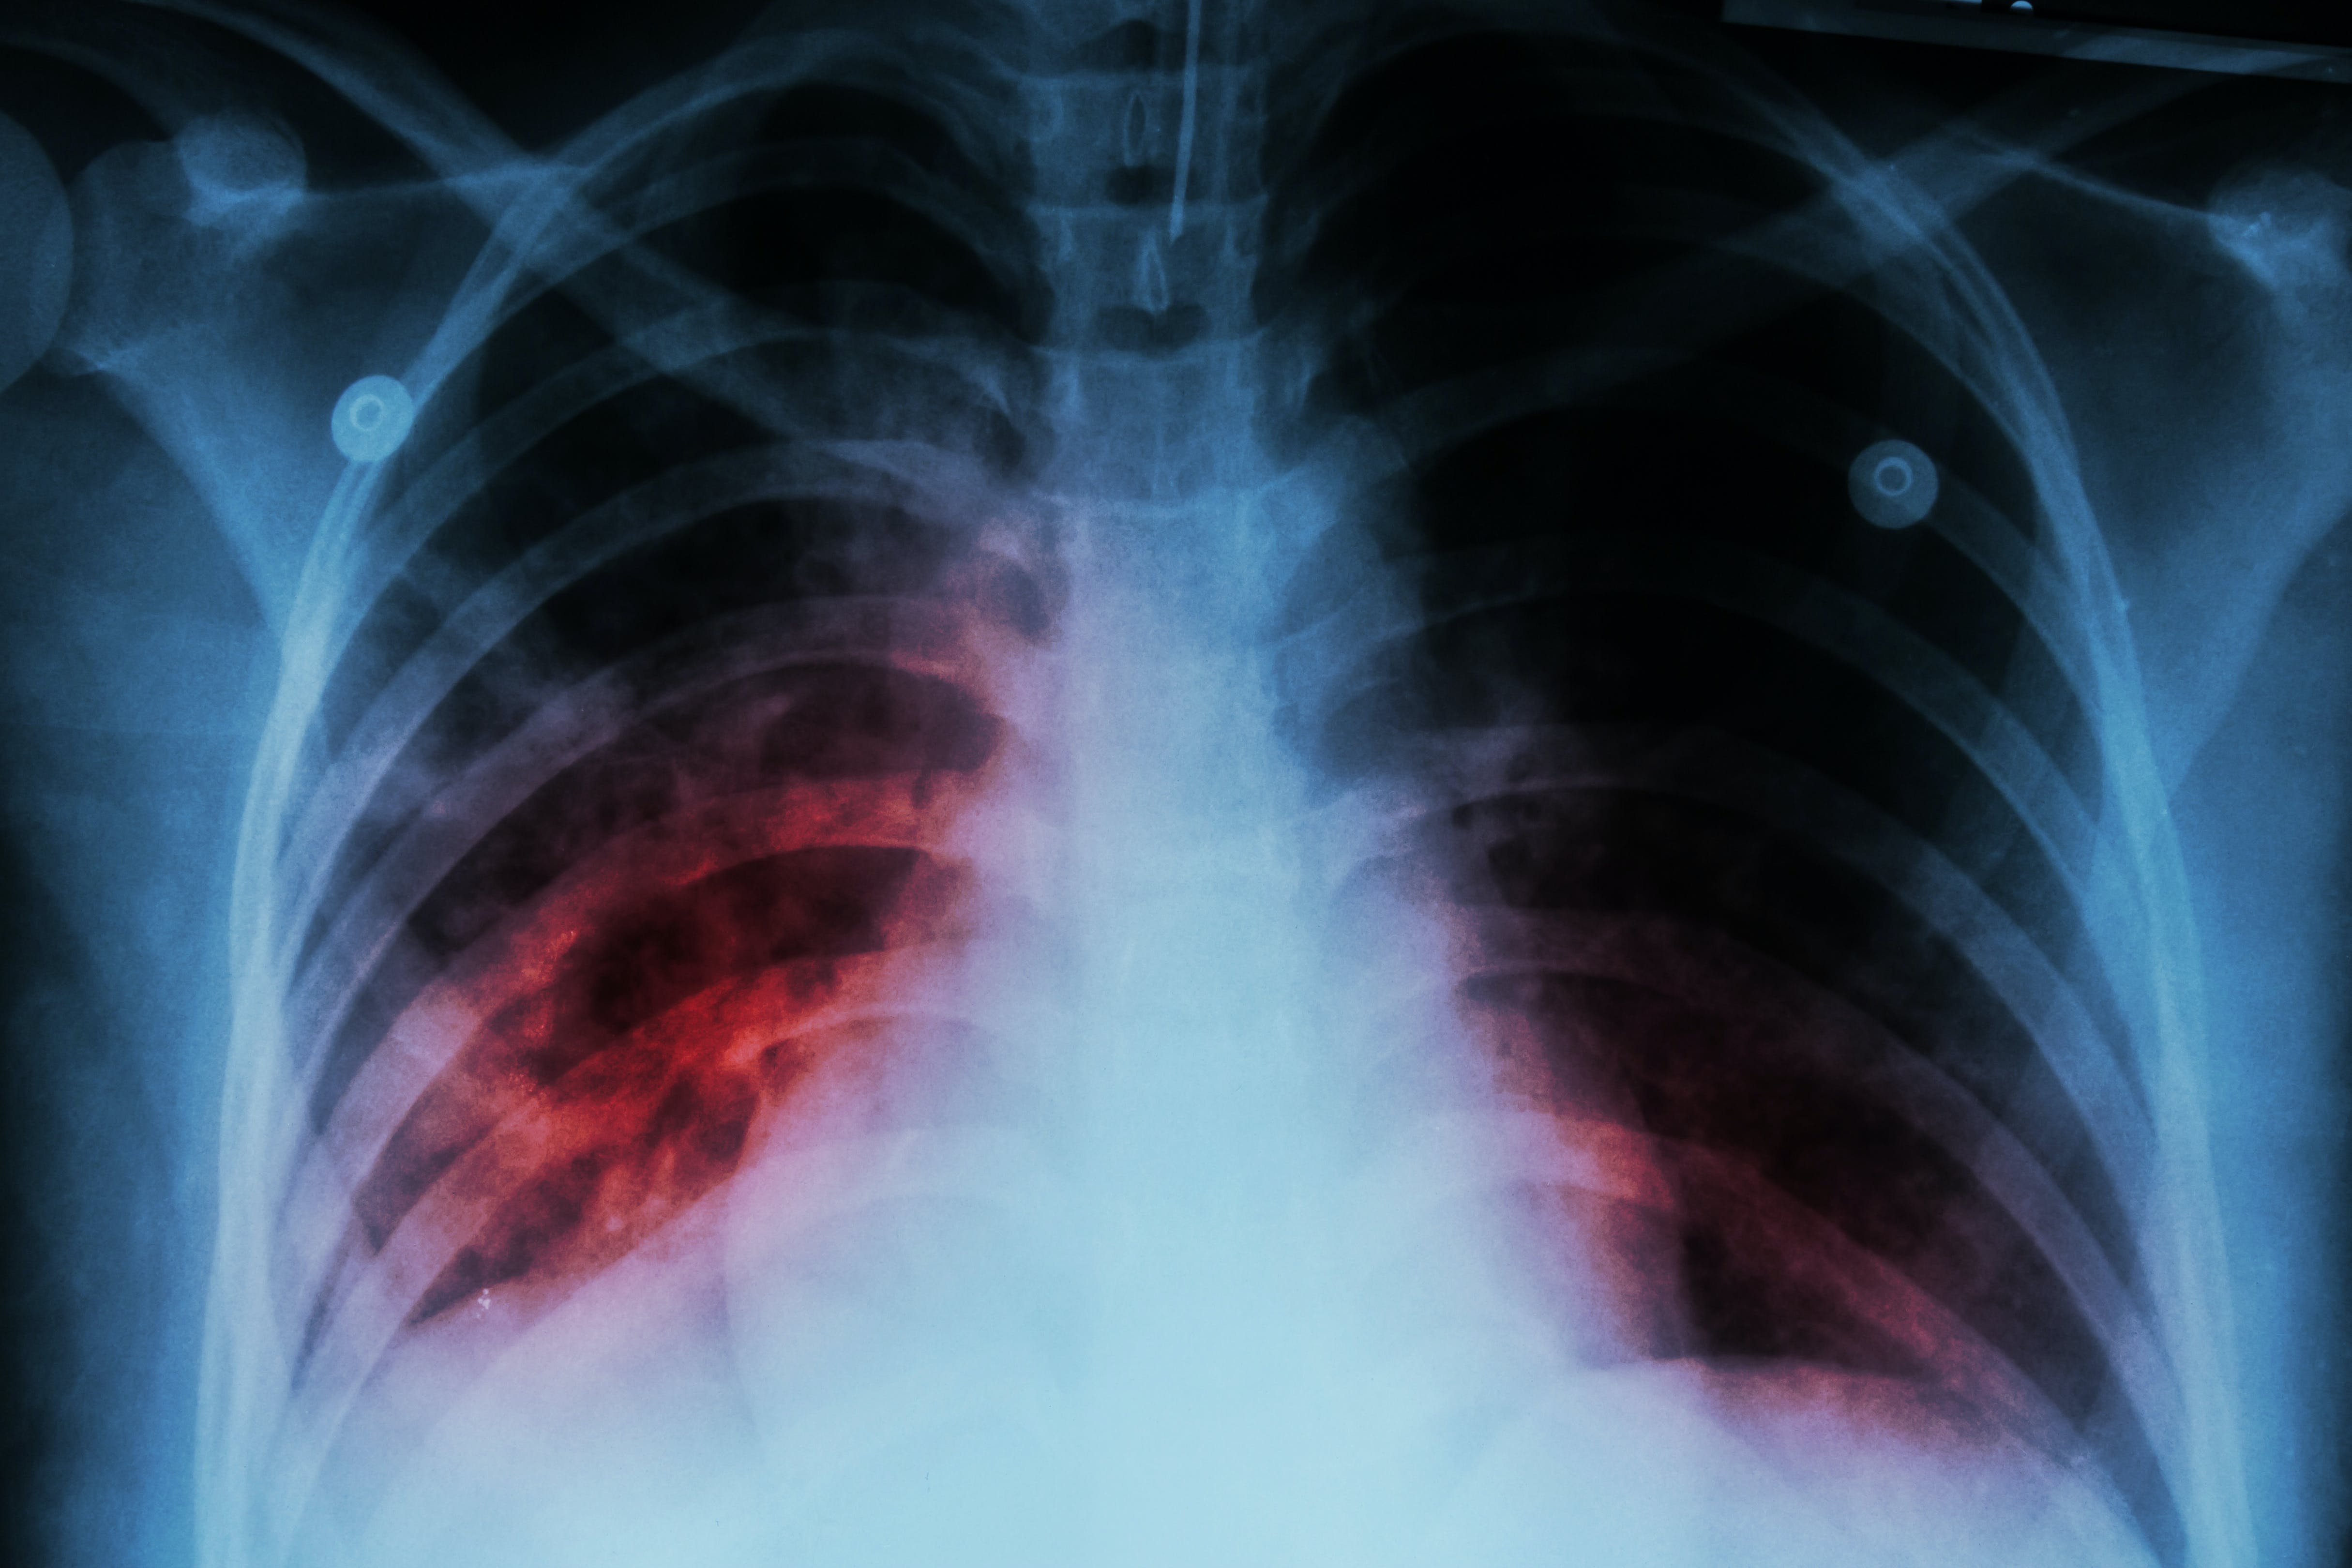

Globally, an estimated 10.6 million people fell ill with TB in 2022, up from 10.3 million in 2021. Geographically, in 2022, most people who developed TB were in the WHO Regions of South-East Asia (46%), Africa (23%) and the Western Pacific (18%), with smaller proportions in the Eastern Mediterranean (8.1%), the Americas (3.1%) and Europe (2.2%).

The total number of TB-related deaths (including those among people with HIV) was 1.3 million in 2022, down from 1.4 million in 2021. However, during the 2020-2022 period, COVID-19 disruptions resulted in nearly half a million more deaths from TB. TB continues to be the leading killer among people with HIV.

Multidrug-resistant TB (MDR-TB) remains a public health crisis. While an estimated 410 000 people developed multidrug-resistant or rifampicin-resistant TB (MDR/RR-TB) in 2022, only about two in five people accessed treatment.